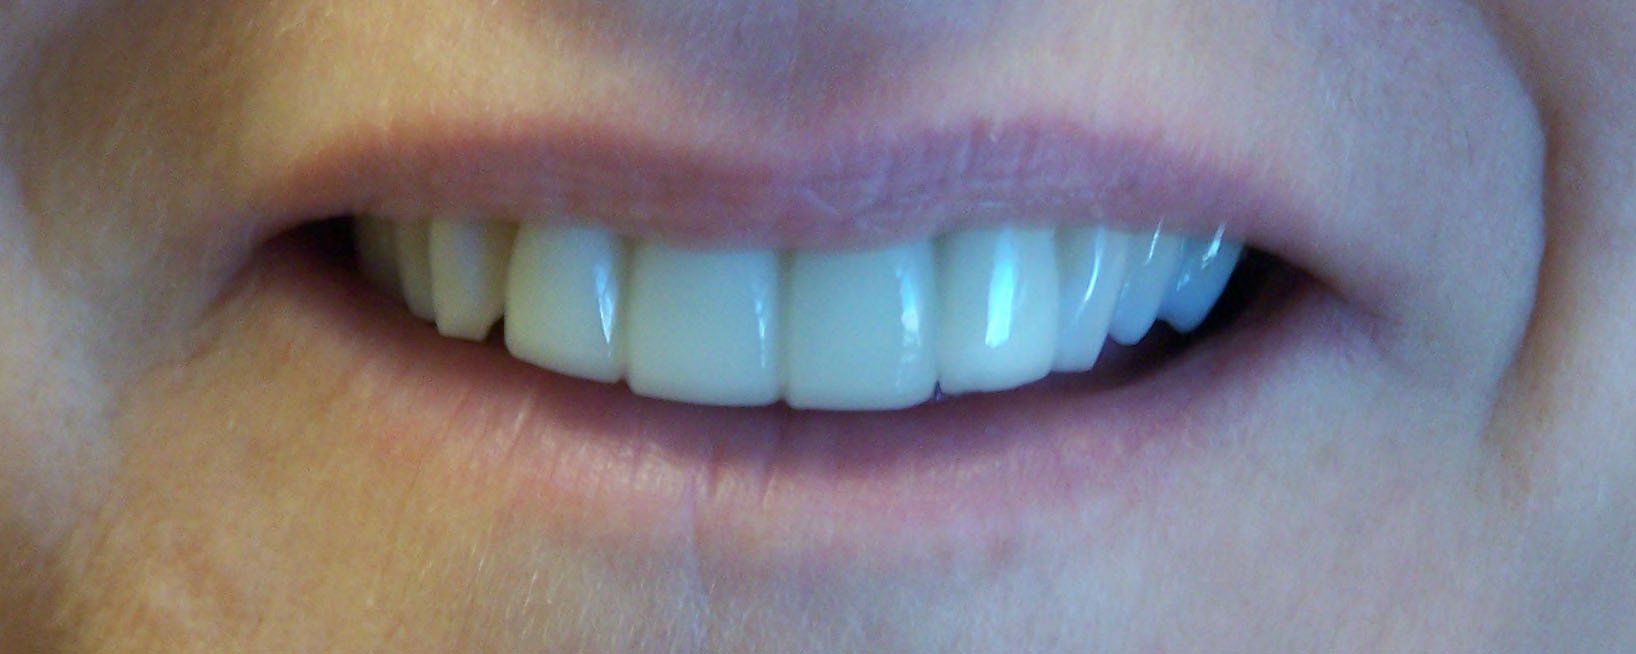

Ally After

Holly After

Karen After

Nancy After